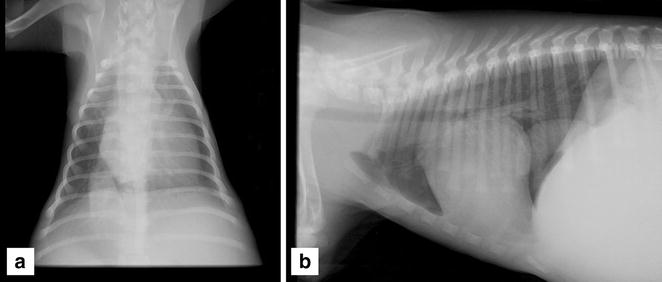

背景:右侧三心房(CTD)是一种罕见的先天性心脏畸形,有多种表现,犬偶发。临床上,犬表现为右心衰或Budd Chiari样综合症的非特异性症状。常见并发心血管畸形。复杂畸形的诊断与充分表征需要仔细调查,通常采用多模态成像方法。一条10周龄、雄性犬出现了发育不良、食欲减退和进行性腹水的临床症状。CTD闭锁与后腔静脉(cdvc)单独分离和并发静脉壁矿化共同地诊断并利用超声心动图、非选择性血管造影、CT血管造影和心脏磁共振成像(MRI)联合诊断。通过手术犬被成功治愈,恢复了正常的活动。结论:这是CTD无从右心房分离cdvc及肝实质矿化研究的第一案例。CTD对幼龄犬的腹水发展是一个重要的和潜在的可纠正的因素。复杂心脏畸形的准确诊断对选择最合适的治疗方案很重要。关键词:三心房 先天性心脏畸形 Budd-Chiari样综合征 血管矿化背景:右侧三房心犬很少发现,总患病率低。这个心脏异常的静脉窦胚胎右阀未能回归,导致右心房(RA)划分成两个独立的腔室和有效地创建一个三心房。纤维膜分裂的RA是最常见的穿孔,但是,在某些情况下,如所描述的,闭锁导致静脉完全阻塞,从身体后半部分或前半部分的回心血液回流障碍。由于在不同情况下出现不同程度的回流失败,从腹部到RA的静脉回流可以受到不同程度的阻碍。这可能会导致临床体征的尾右心充血性心力衰竭(CHF)或Budd-Chiari综合征。因此,替代途径包括腔静脉、静脉分流,以确保静脉从四肢和腹部返回到右心房是可能的。既然CTD可以出现各种并发心脏畸形,包括三尖瓣发育不良、动力性主动脉瓣下狭窄,心房间隔缺损(ASD)、肺动脉瓣狭窄,卵圆孔未闭(PFO),室间隔缺损,心包缺如、左颅腔静脉或Ebstein畸形,这可能会影响结果,仔细评估每个个案确定CTD修正将解决临床症状,给患者造成了一个有利的结果是很重要的。从多模态影像诊断方法,为了更准确地描述这种复杂的心血管畸形,帮助确定最适当的治疗方法。本文报告一例CTD幼龄犬使用各种成像方式的表征。案例:10周龄犬,雄性,诊断发现生长发育迟缓,厌食症和腹胀的临床症状。胸部和腹部X光片显示明显的cdvc扩张和肝肿大。体格检查,腹部下垂,腹胀,触诊出现腹壁紧张。尽管心动过速,肺音听诊被视为正常,没有听到心脏杂音、心律失常或颈静脉扩张。六导联心电图无异常。粘膜苍白但湿润,毛细血管充盈时间正常。全血细胞计数、血清生化轮廓显示轻度低蛋白血症(29 g/L)和中度小细胞低色素性贫血(红细胞压积:22%)有明显再生的证据。餐前及餐后血清胆汁酸均正常。胸部X光片显示重复的严重扩张和cdvc曲张。轻度右心增大。重度肝肿大和减少腹腔浆膜细节提示出现腹水。腹部超声证实严重的cdvc扩张,肝静脉明显充血,严重肝肿大和少量的游离腹水。检测有胆囊结石。多普勒超声检查心室内无血液流动。基于这些初步发现,怀疑这种扩张的cdvc被下腔静脉-心房交界处的膜完全包围,从而初步诊断CTD有无心房膜。没有其他并发心脏异常,进行对比增强超声心动图检查帮助确诊是否颅腔静脉、cdvc和RA之间有通道。右头静脉注射生理盐水,RA立即发现微泡确认前腔静脉(CrVC)和RA之间的正常通道。在左侧隐静脉内注入兴奋性生理盐水,大量的微泡通过RA进入右心室。只有少数的微泡出现在前腔静脉。在CdVC中腹部,在不进行持续向前运动的情况下观察到大量的微泡吸入和逆行。这一发现表明,CdVC和RA之间没有通道微泡经交替静脉途径到达右心。用碘海醇静脉对左侧大隐静脉非选择性血管造影证实静脉通过前腔静脉回流到心脏。在扩张的右奇静脉(直接进入RA)确定了对比度。在全身麻醉下使用16层螺旋CT扫描仪进行胸部和腹部的计算机断层血管造影(CTA)。术前和碘海醇注射到侧大隐静脉1, 2和3分钟之后获得图像。由细的不规则的矿物致密材料线性累积在一个面积约22×L 16毫米形成异常组织。超声时这一区域已显示为强回声。注射造影剂后,一个显著的扩张右奇静脉进入RA。cdvc扩张穿过膈延伸到腹腔,肝静脉明显扩张。确认肝静脉回流至心脏及继发性肝淤血。并发现多灶性点状肝实质的矿化。心脏MRI研究对心脏和主要胸部血管进行进一步的结构和功能评估。前腔静脉的血流以及右奇静脉扩张,通过腔静脉窦和脑RA和进入右心室畅通。冠状窦进入右房房腔也正常,在心动周期的各个阶段,cdvc和RA之间的无血管流确认正常尾静脉回流至RA的完全梗阻。人类儿科心脏病专家关于这种情况的建议,使用球囊扩张或切割球囊进行介入治疗不是可行的选择,因此两周后,在轻度低体温的情况下,在完全静脉闭塞的情况下进行手术矫正。心脏是通过右第五肋间开胸,从胸腔抽吸100毫升的轻度混浊胸腔积液。部分分离cdvc和RA的膜被切除,创建一个约1-2cm的切口。总流入阻断时间为2分钟,心脏始终跳动。静脉血流恢复后立即显著减少cdvc扩张和改善RA填充。麻醉顺利恢复。术后,狗开始服用低剂量阿司匹林,以减少血栓形成的风险(5毫克/公斤,连续7天)。术后一周超声心动图显示心功能正常,cdvc扩张良好,胸腹部肿胀消失。两个心房正常充盈,胸腔积液消失,肝叶周围少量腹腔积液。一个月后,心脏功能和cdvc大小正常。此后,犬逐渐恢复正常活动,生长迅速,表现出正常的运动耐力。结论:本病例报告描述了一种罕见的先天性心脏畸形导致从cdvc一无孔膜导致的三心房。本案独特的方面是cdvc分离膜的位置不寻常和肝实质并发矿化。。CTD对幼龄犬的腹水发展是一个重要的和潜在的可纠正的因素。复杂心脏畸形的准确诊断对选择最合适的治疗方案很重要。